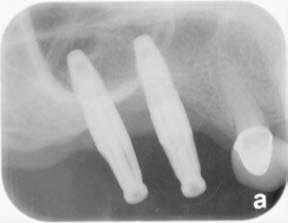

Figure 5: Pre-op X-rays showing the presence of peri-implantitis with bone loss

A 50-year-old female, nonsmoker, with noncontributory medical history came in for a routine checkup. Clinical examination revealed increased pocket depths around two maxillary implants and bleeding upon probing. The pocket depths ranged between 5 mm-8 mm facially and 4 mm-9 mm lingually. Preoperative X-ray showed circumferential bone defects around both implants (Figure 5). Diagnosis of peri-implantitis was made with the bone loss to the 3-5 threads of the implants. The possible causes include bacterial invasion of the titanium surface, occlusal trauma, and anatomical placement issues relative to the crest of bone, obstructing access for maintaining oral hygiene.